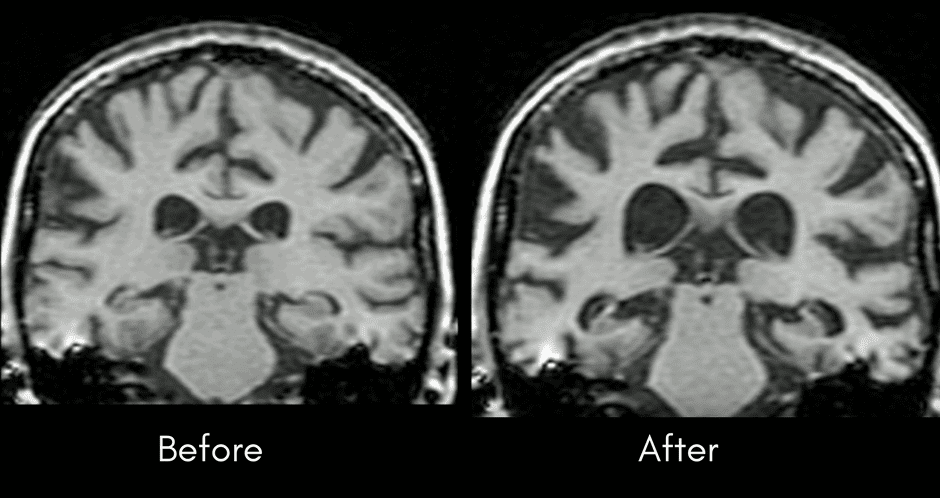

When a person has Dementia, one of the changes that occurs over time is that the size of a person’s brain decreases as brain cells die.